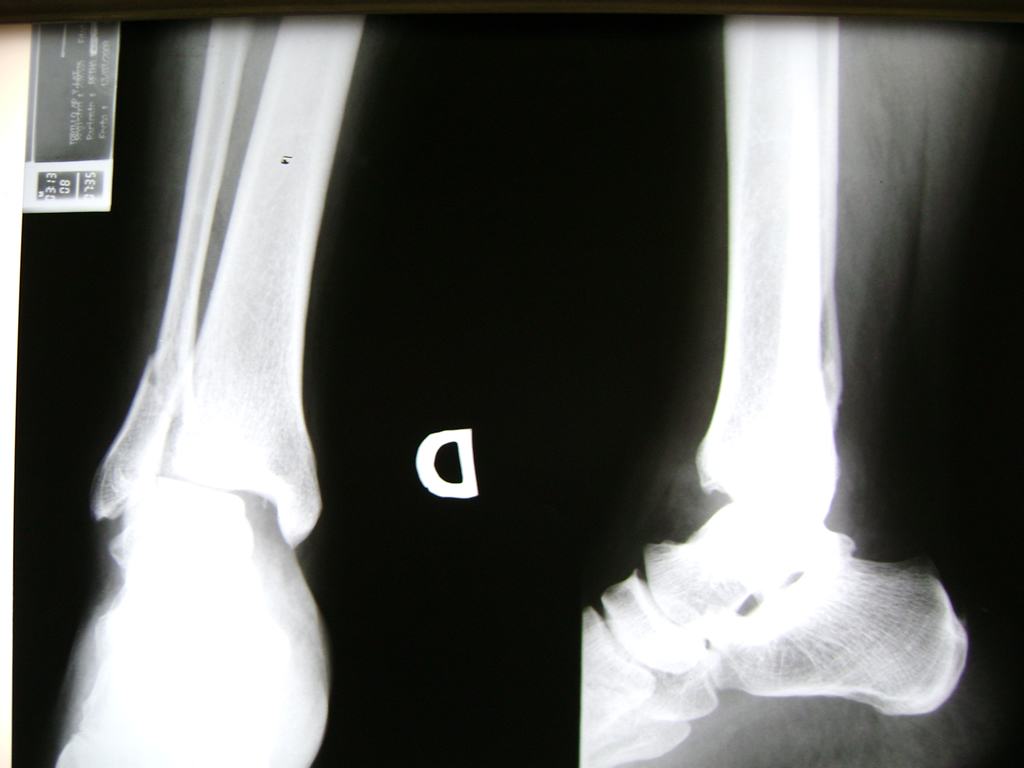

Una fractura de tobillo es la rotura de uno o más de los huesos del tobillo. Estas fracturas pueden ser:

- Parciales (el hueso está sólo parcialmente fisurado, no del todo).

- Completas (el hueso está perforado y está en 2 partes).

Algunas fracturas de tobillo pueden requerir cirugía si:

- Los extremos de los huesos están desalineados entre sí (desplazados).

- La fractura se extiende hasta la articulación del tobillo (fractura intra-articular).

- Los tendones o ligamentos (tejidos que sujetan los músculos y los huesos entre sí) están rotos.